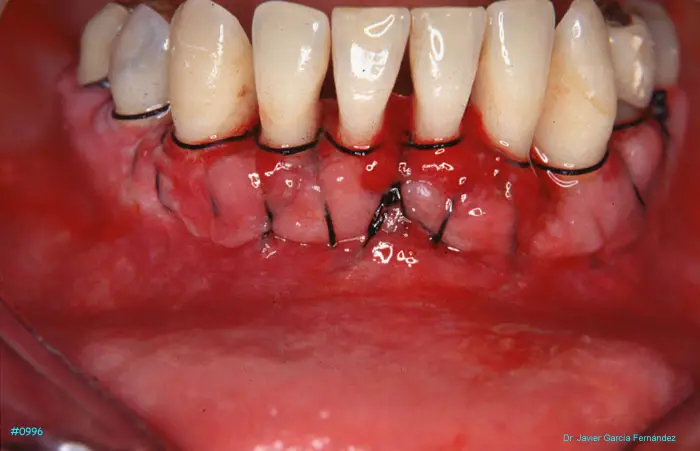

Atlas of Surgical Techniques in Periodontics. Chapter III. Atlas de Técnicas Quirúrgicas en Periodoncia